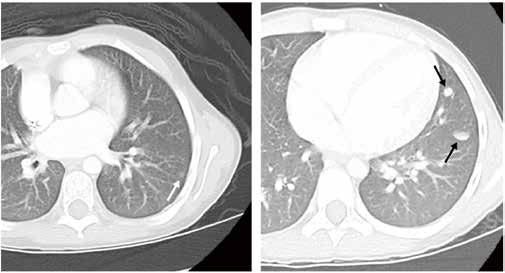

2个周期的长春新碱、放线菌素D、多柔比星(DD-4A方案)化疗后,研究者采用胸部CT评估肺结节应答情况,以确定肺结节快速完全缓解(RCR)队列和肺结节缓慢的不完全缓解(SIR)队列;在两个队列中比较肺转移数量和大小对无事件生存(EFS)和总生存(OS)的影响,其中RCR队列接受额外的DD-4A方案但不接受肺部放疗,SIR队列接受原来的三药加环磷酰胺/依托泊苷(M方案)并配合肺部放疗。

结果显示,AREN0533试验共招募288例仅伴肺转移的Ⅳ期患儿,其中251例符合纳入标准并接受分析。在RCR队列(105例)中,肺转移数量对EFS和OS无显著影响;肺转移大小显著影响EFS(P=0.022),但对OS无显著影响。在SIR队列(146例)中,肺转移数量或大小对EFS和OS均无显著影响。

在多变量模型中,肺转移数量和大小对EFS或OS均无显著的相关性 ;但校正了这些因素后,1q增益仍与生存显著相关(EFS:P=0.0015;OS:P=0.039)。